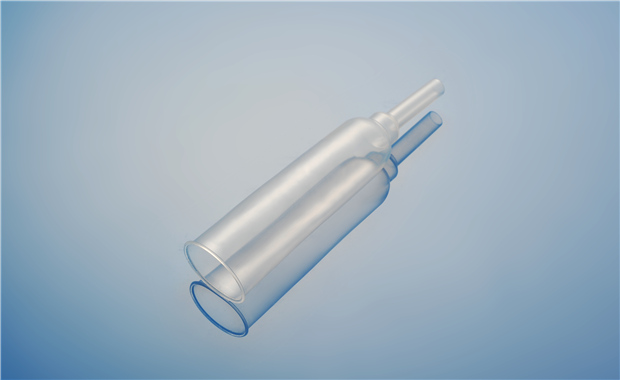

【產品名稱】一次性使用單腔導尿管(PVC兒童型) 【型號規格】6Fr、8Fr��、10Fr 【性能��、主要結構】 由醫用PVC粒料為主要原材料制成��,由排泄錐形接口���、管身、排尿孔組成�����。

【產品名稱】一次性使用單腔導尿管(PVC成人型) 【型號規格】12Fr、14Fr���、16Fr���、186Fr、20Fr���。 【性能���、主要結構】 由醫用PVC粒料為主要原材料制成,由排泄錐形接口��、管身��、排尿孔組成�����。